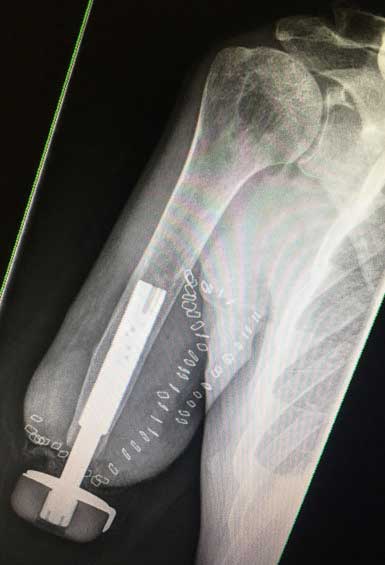

Der Eingriff erfolgt in Vollnarkose und erfordert ein interdisziplinäres Team aus Orthopäden und Plastischen Chirurgen. In der Klinik der Autoren wird das OPRA-Implantat (“Osseoanchored Prosthesis for the Rehabilitation of Amputees”; Fa. Integrum, Schweden) verwendet. In einer Operation wird der intramedulläre Anteil der Prothese implantiert, mit Hilfe eines Schraubsystems verankert und dann der Hautaustritt plastisch konstruiert. Der externe Anteil des Implantats wird ausgeleitet. Der präparierte Hautmantel wird dann inklusive des Hautaustritts vorsichtig umgeschlagen, damit der mikrochirurgische Nerventransfer nach Präparation der Armnervenneurome und Empfängernerven erfolgen kann (Abb. 2a–d).

Eine intraoperative Durchleuchtung dokumentiert den exakten Sitz des Implantats im Markraum. Postoperativ erhalten alle Patienten 3 Monate lang 1000 mg Calcium und 2000 Einheiten Vitamin D, um die Osseointegration zu unterstützen. Auf nichtsteroidale Antirheumatika (Ibuprofen etc.) sollte verzichtet werden, da sie den Prozess beeinträchtigen können.